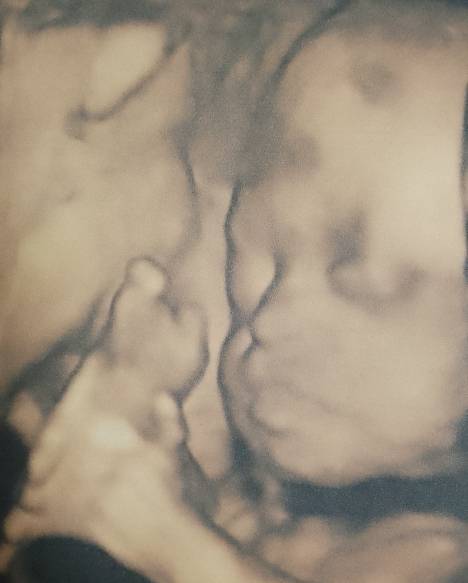

Сходила на 3д узи. Доча уже 960 гр, опережаем по размерам на нелелю)))

Мы в 27 недель были 1010 грамм))вы большие ))Аллох1умма барик(от сглаза)